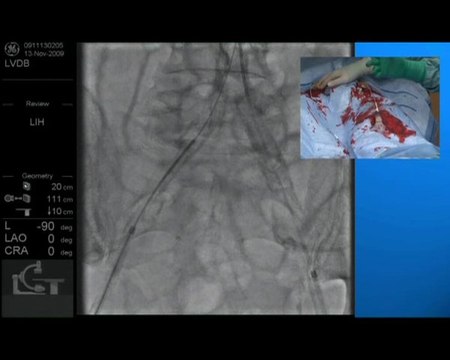

11 left superficial artery recanalization and stenting drug eluting stent incathlab.com

left, superficial, artery, recanalization, stenting, drug, eluting, stent, incathlab